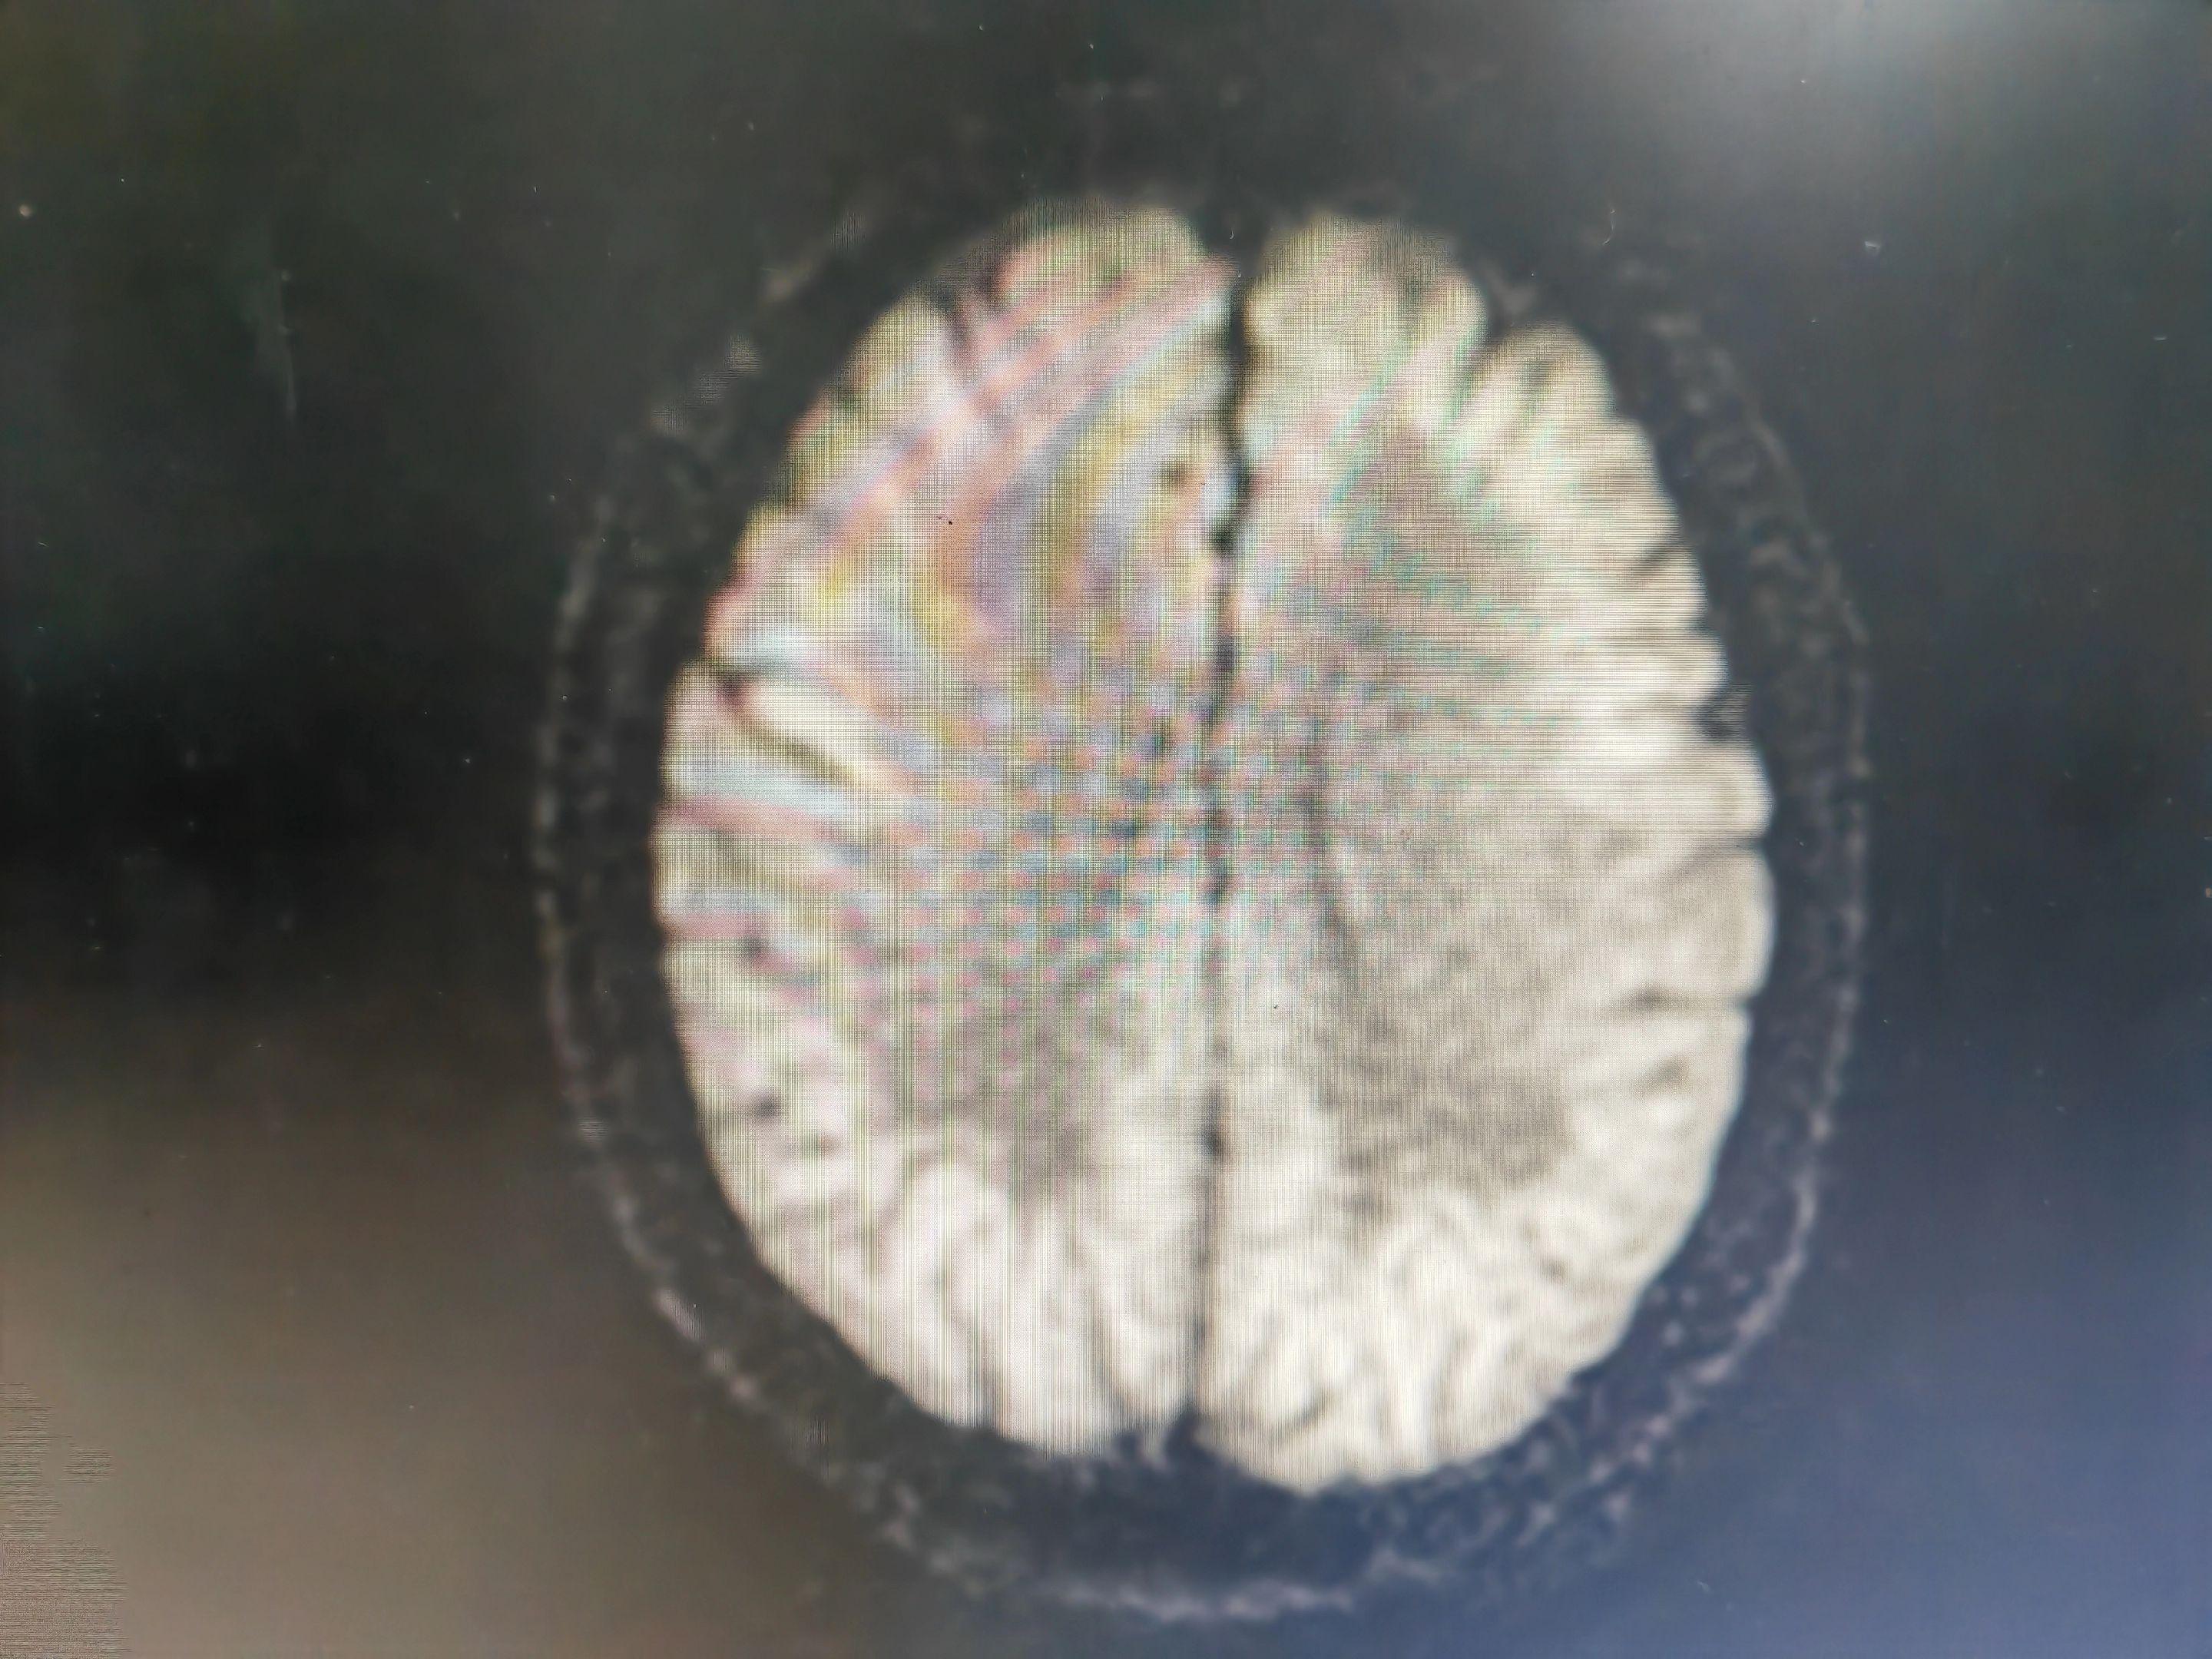

意识模糊伴言语不清的病人 中毒代谢性脑病几种最重要的影像学表现:白色即为受累区域,包括双侧对称性基底节和/或丘脑受累(图A),对称性齿状核受累(图B),皮层灰质受累(图C),对称性脑室周围白质受累(图D),皮质脊髓束受累(图E),胼胝体受累(图F),不对称性白质受累(脱髓鞘疾病;图G),枕顶枕部血管源水肿(图H),脑桥中央受累(I)。